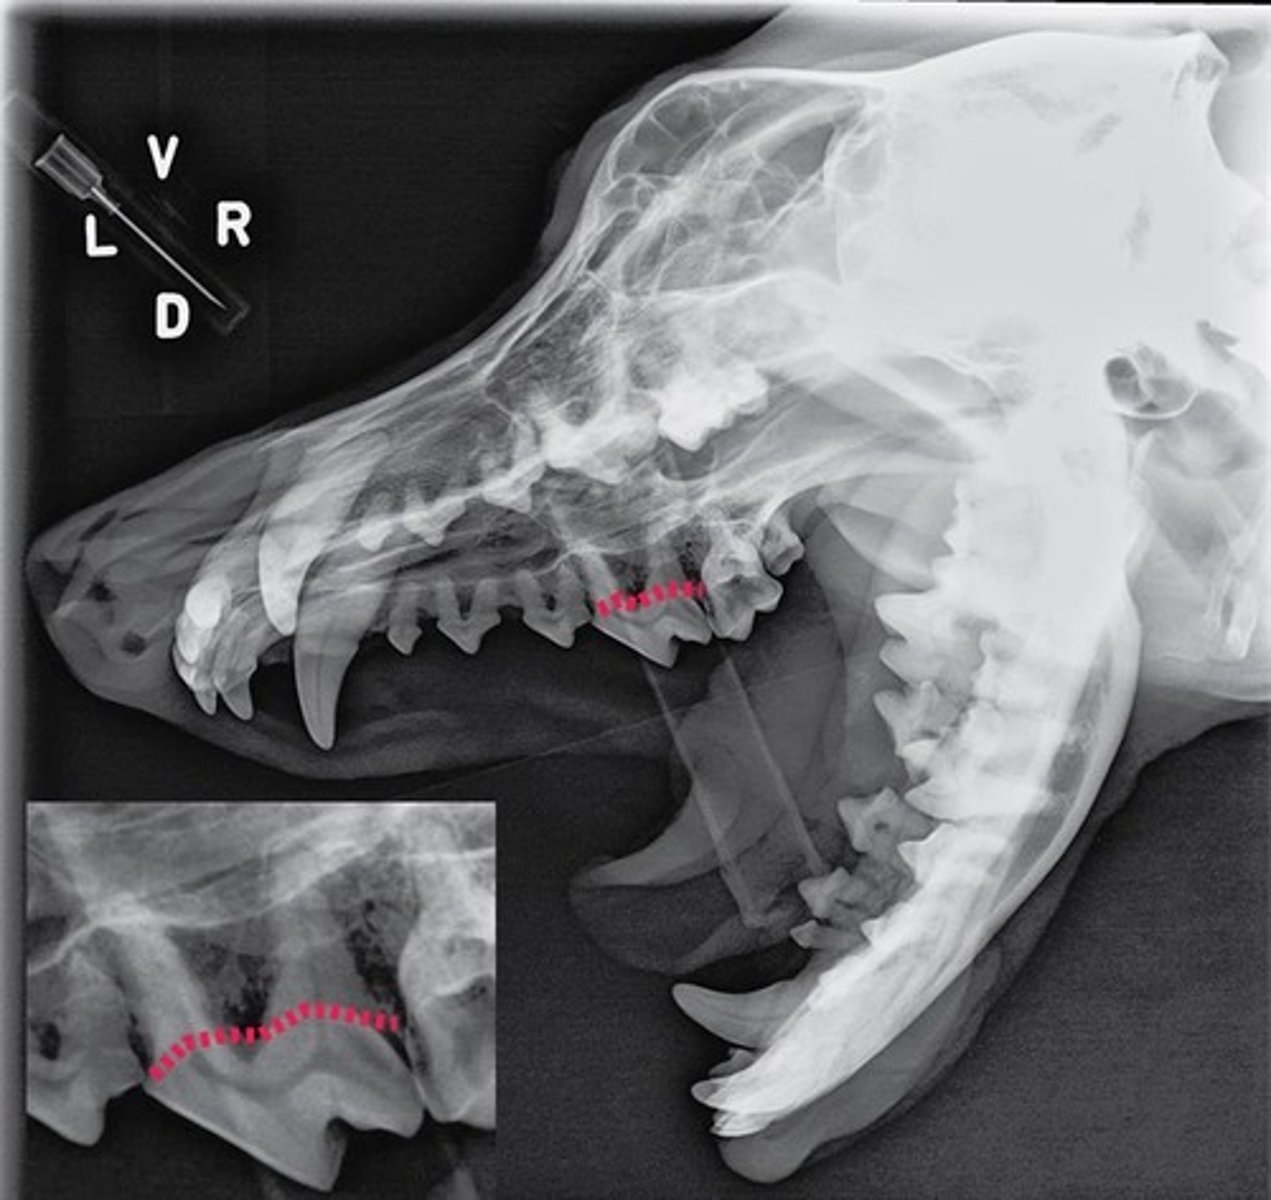

Identify the type of tooth indicated by the arrow.

Molar

Identify the type of tooth indicated by the arrow.

vestibular, buccal, facial surface

Identify the tooth surface the red line being pointed to by an arrow represents

lingual surface

Identify the tooth surface the red line being pointed to by an arrow represents

mesial surface

On the first molar, identify the surface the red line being pointed to by an arrow represents.

distal surface

On the first molar, identify the surface the red line being pointed to by an arrow represents